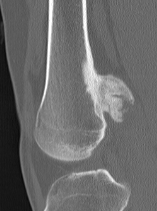

CT

Can be used to differentiate from osteochondroma

1. Parosteal OS

- attached to cortex growing into soft tissue

- normal cortex intact

Parosteal Osteosarcoma proximal tibia